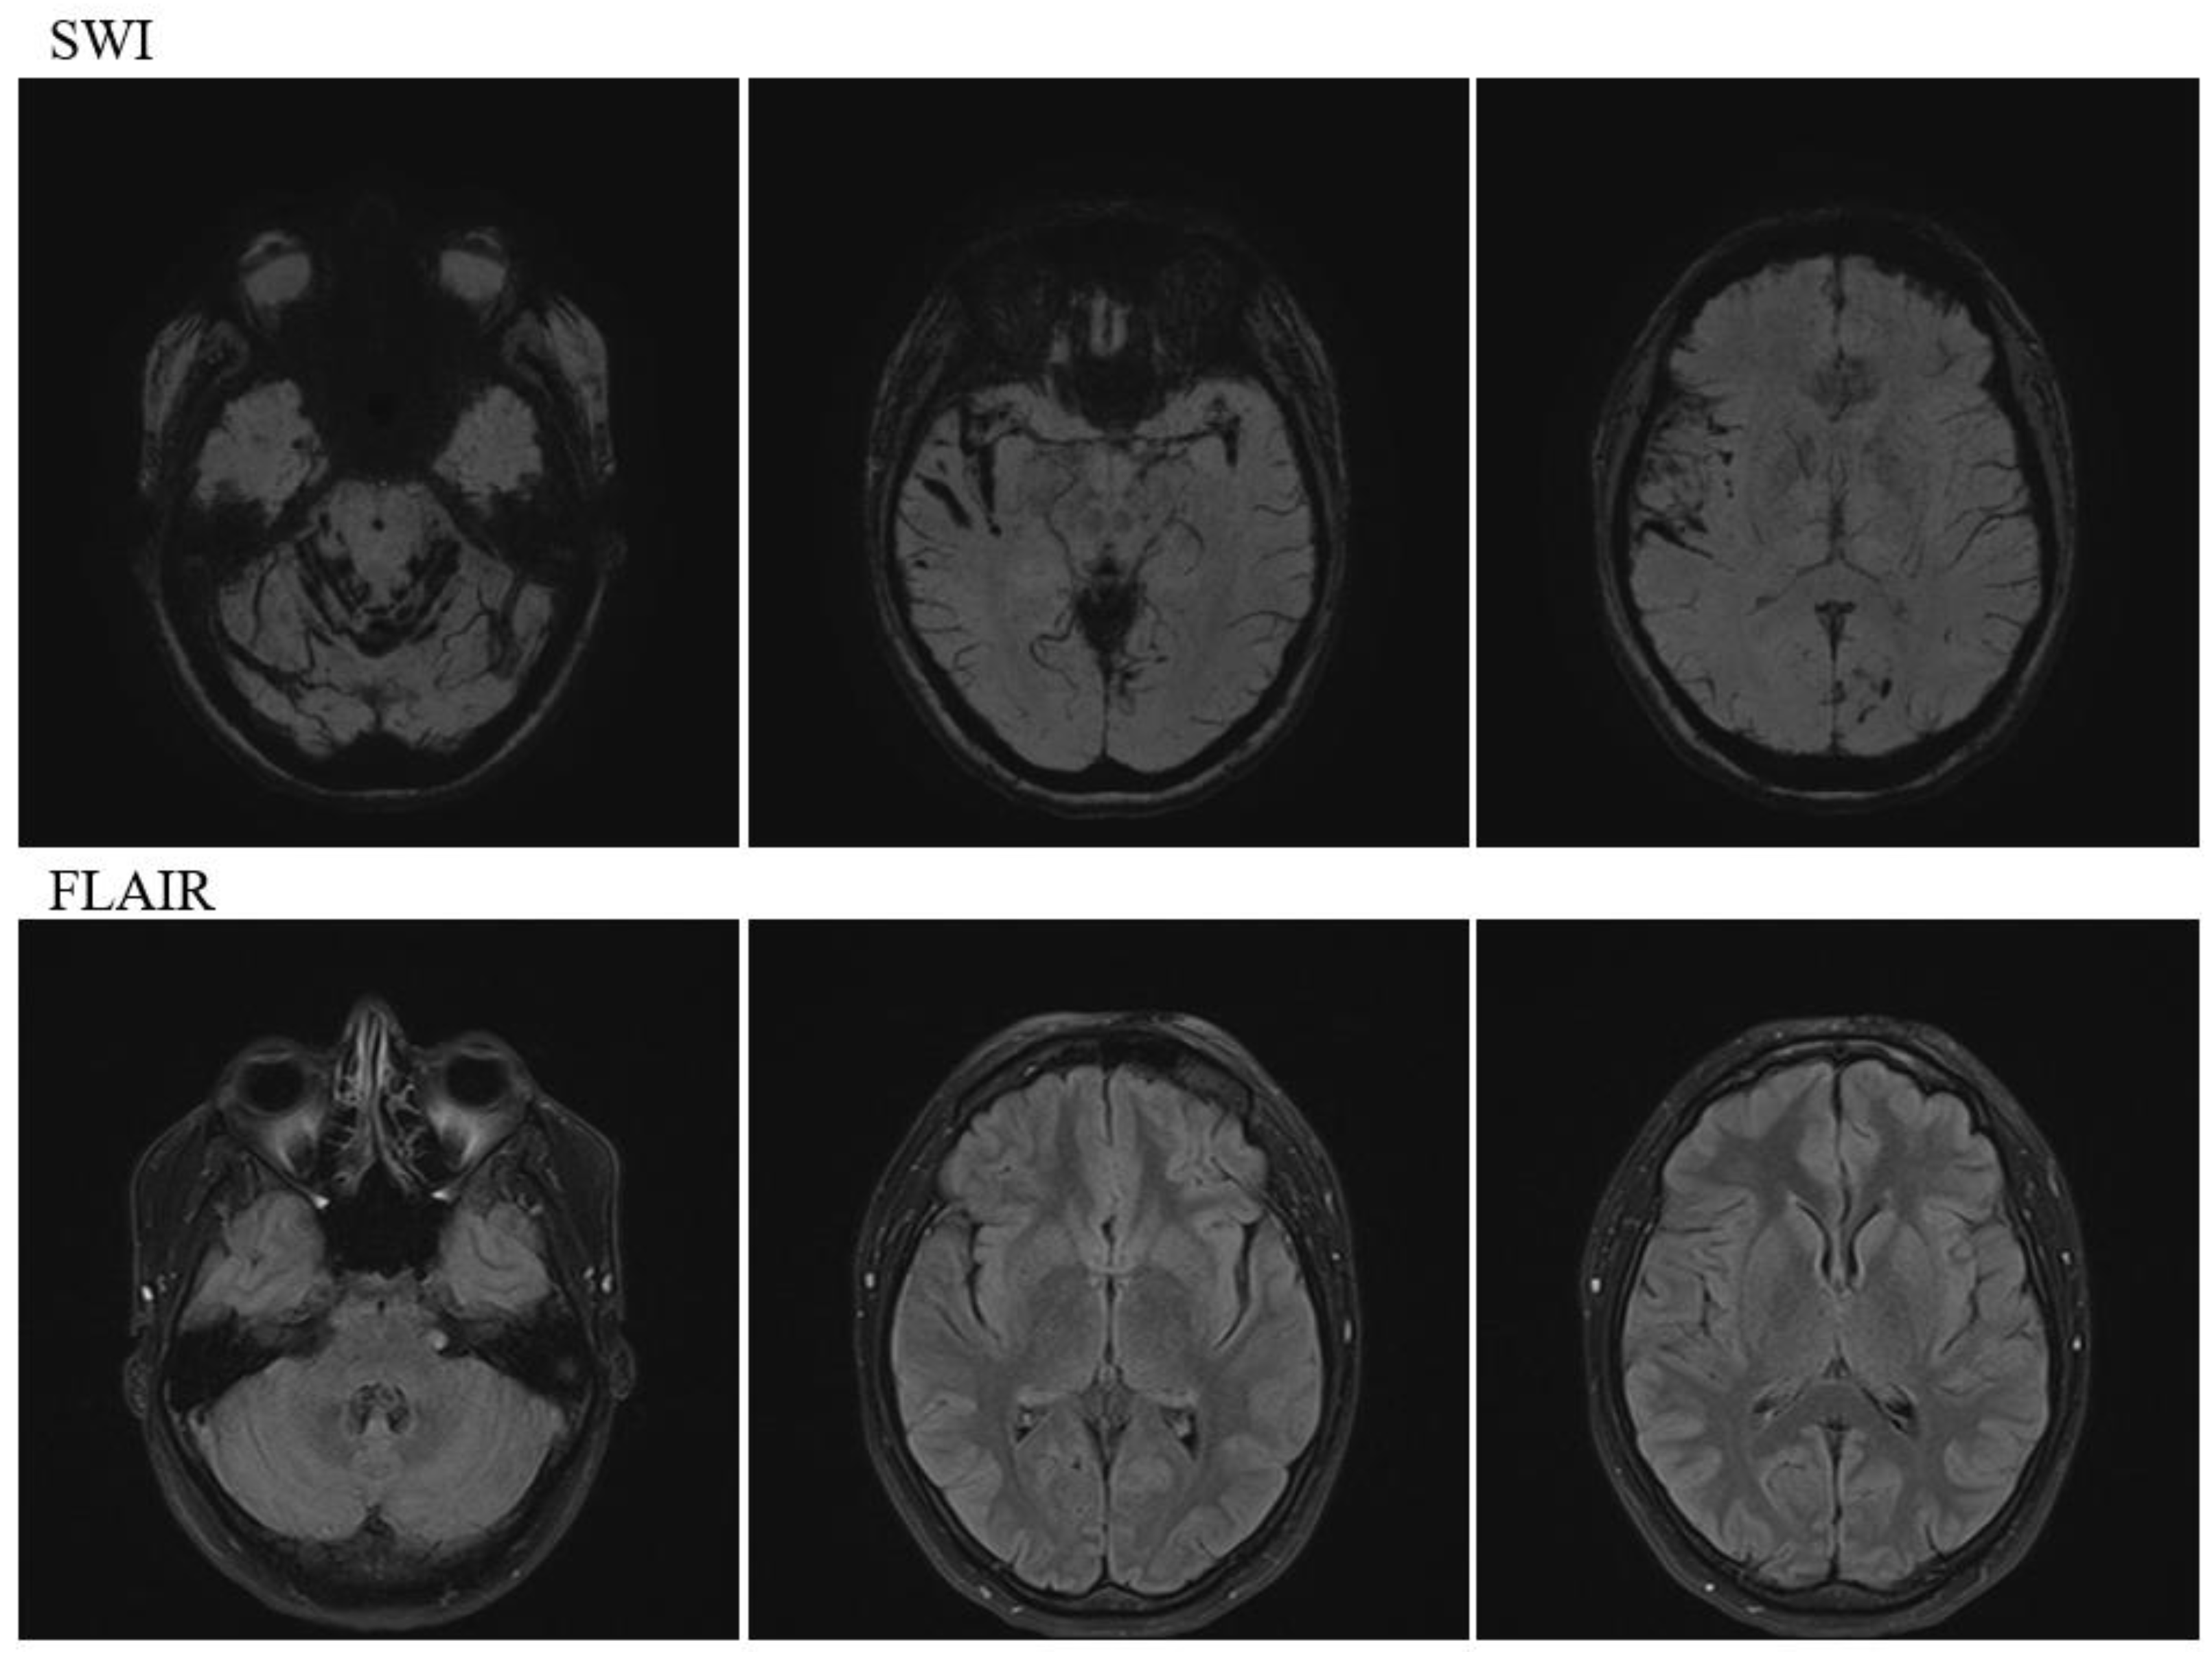

Head magnetic resonance imaging (MRI) (Figure 2) revealed multiple prominent hemosiderin deposits on the cerebellar surface and similar hemosiderin deposits in the temporal lobe and fissure sylviae, indicating infratentorial and cortical SS.

Figure 2. Magnetic resonance imaging on admission. SWI showing low findings on the cerebellar hemispheric surfaces and cranial nerves under the cerebellar tent and low findings on cortical surfaces, such as the Sylvian fissure on the tent. SWI: susceptibility-weighted imaging, FLAIR: fluid attenuated inversion recovery